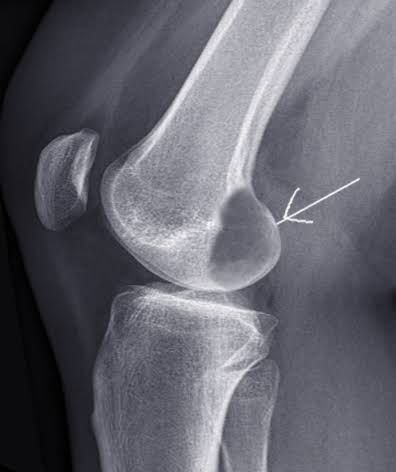

The giant cell tumor of bone (GCTB), also known as an osteoclastoma or a myeloid sarcoma, is a benign local aggressive osteolytic neoplasm that primarily affects skeletally mature young adults. These usually arise in the metaphysis and extend into the epiphysis of long bones.